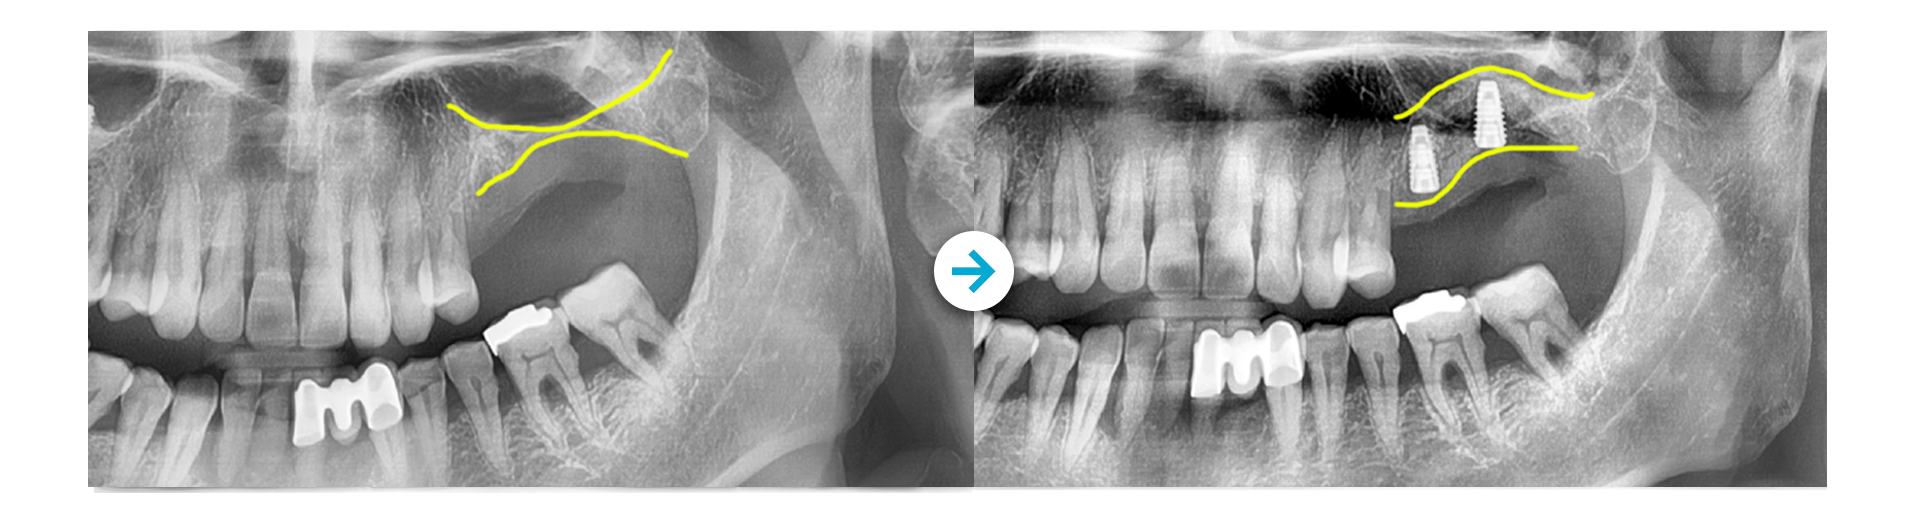

상악동거상술

상악에 임플란트를 식립할 만한 잇몸뼈가

충분치 않은 경우 상악동의 하방 벽을 들어 올려

공간을 확보하는 시술으로

해당 부위에 뼈이식을 실시해 골 형성을 유도하고

회복해 안정적인 임플란트 식립을 가능케 합니다.

뼈이식 후 임플란트 식립

Before 사진 촬영일자: 2018.01.08 /  After 사진 촬영일자: 2021.06.08

상악에 임플란트를 식립할만한 잇몸뼈가 충분치 않은 경우

상악동의 하방벽을 들어올려 공간을 확보하는 시술으로

해당부위에 뼈이식을 실시해 골형성을 유도하고 회복해

안정적인 임플란트 식립을 가능케 합니다.